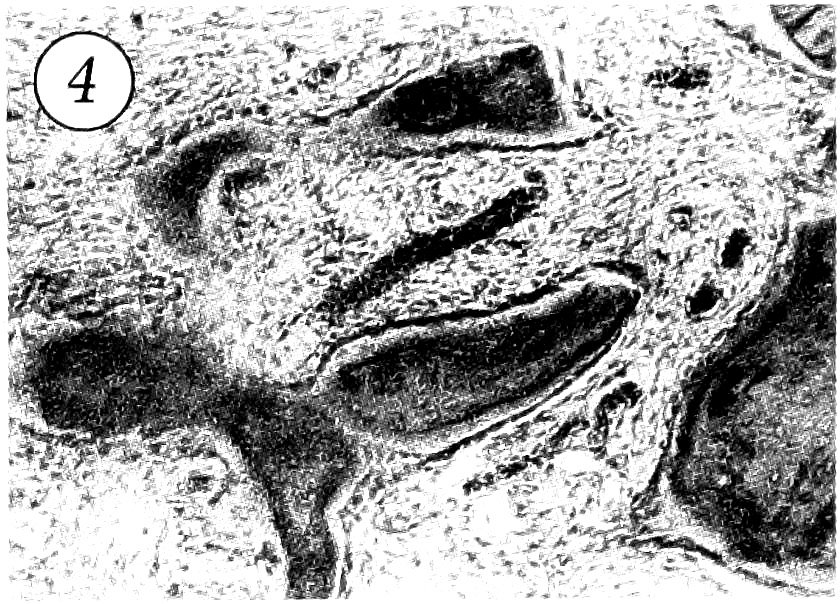

При морфологическом исследовании патологический очаг был представлен фиброзной тканью, окружающей костные трабекулы различной степени зрелости (рис. 3). В центре очага обычно преобладала фиброзная ткань, тогда как костные трабекулы располагались в основном в периферических участках. Фиброзная ткань состояла из относительно рыхло упакованных пучков коллагеновых волокон и клеточных элементов, среди которых превалировали хорошо дифференцированные фибробласты. Пучки коллагеновых волокон иногда формировали «муаровый» рисунок. Из других клеточных элементов в основном определялись гистиоциты и локальные скопления остеокластоподобных гигантских многоядерных клеток. Характерным признаком заболевания была «зональность» архитектоники патологического очага. При этом в центре располагались редкие, относительно тонкие, незрелые трабекулы примитивного или эмбрионального типа, тогда как в периферических участках — более многочисленные, широкие и более зрелые костные трабекулы, имеющие различной степени выраженности пластинчатое строение. В большинстве случаев костные трабекулы были ограничены цепочкой крупных остеобластов с базофильными ядрами (рис. 4).

Рис. 3. В патологическом очаге кортикальная кость замещена фиброзной тканью с отдельными костными трабекулами. Окраска гематоксилином и эозином. Ув. 100.

Рис. 4. Костные трабекулы, имеющие пластинчатое строение, окружены цепочками остеобластов. Окраска гематоксилином и эозином. Ув. 160.